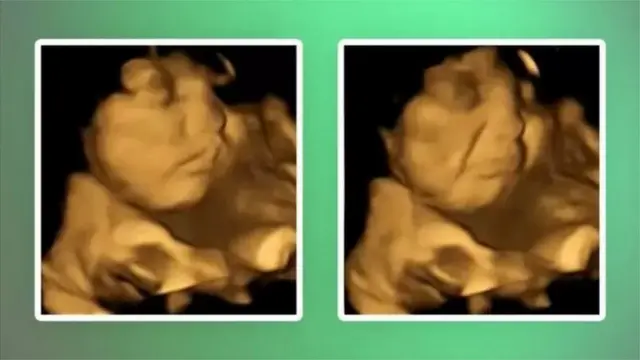

ઇમેજ સ્રોત, FETAL AND NEONATAL RESEARCH LAB/DURHAM UNIVERSITY

ઇંગ્લૅન્ડની આ યુનિવર્સિટીએ 100 ગર્ભવતી મહિલાઓ પર સંશોધન કર્યું અને શોધ્યું કે ગર્ભમાં વિકસી રહેલાં બાળકોના ચહેરા પર ખાવાની કૅપ્સ્યૂલને લઈને પ્રતિક્રિયા જોવા મળી હતી.

ડરહમના સંશોધક બેયજા ઉસ્તુને આ સંશોધનનું નેતૃત્વ કર્યું હતું, જેમાં માતાઓને લીલાં શાકભાજી અને ગાજરની એક-એક કૅપ્સ્યૂલ આપવામાં આવી હતી.

કૅપ્સ્યૂલ આપ્યા પહેલાં અને એ બાદ ગર્ભમાં વિકસી રહેલા બાળકના ચહેરાનો અભ્યાસ કરવામાં આવ્યો, તેમાં જાણવા મળ્યું કે જ્યારે બાળક સુધી ગાજરની કૅપ્સ્યૂલનો સ્વાદ પહોંચ્યો ત્યારે બાળકનો 'હસતો ચહેરો' જોવા મળ્યો.

જ્યારે માતાને લીલાં શાકભાજીની કૅપ્સૂલ આપવામાં આવી, તો બાળકે 'રડવા જેવો ચહેરો' બનાવીને પ્રતિક્રિયા આપી હતી.

બેયજાએ જણાવ્યું કે, "સ્કૅન દરમિયાન કેળાં અને ગાજર આપ્યાં બાદ ગર્ભમાં રહેલાં આ બાળકોની પ્રતિક્રિયા જોવાની પ્રક્રિયા અને માતાપિતા સાથે એ પળ શૅર કરવાનો અનુભવ પણ અદભુત હતો."